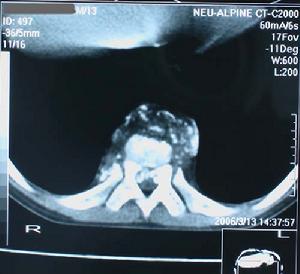

6.X線攝片顯示不規則骨質疏鬆、脫鈣、死骨、骨空洞和寒性膿腫陰影等,晚期關節間隙變窄或消失,呈畸形。

本病診斷主要依據臨床症狀及X射線,同位素骨掃描、病理檢查得以確診。X射線表現一般可呈溶骨性、生骨性或兼有溶骨性和生骨性等不同表現,以溶骨性為多見。骨掃描更具有早診斷的作用。骨腫瘤的治療